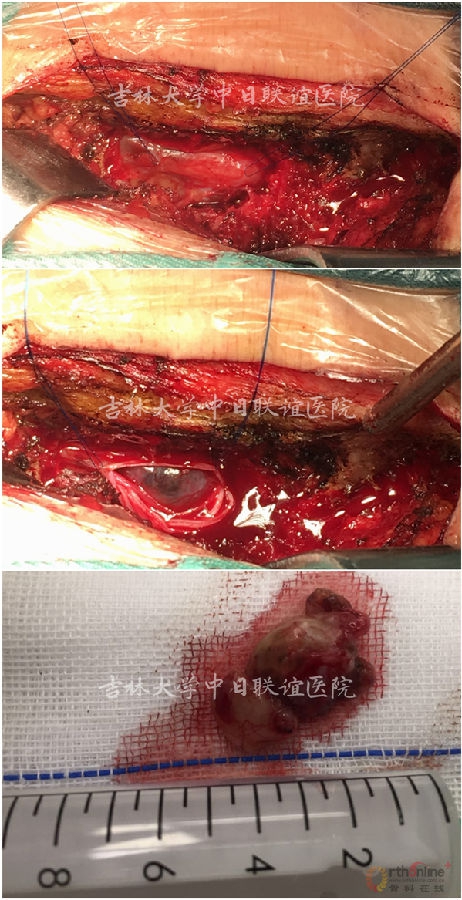

2.暴露目标节段半椎板,开一个宽约1-1.5cm的窗口(如下图) 。

4.(1)标志线提拉(2)纵行切开硬脊膜(3)撕开蛛网膜,放出局部脑脊液(4)沿着肿瘤与脊髓和神经根的分界处进行分离。( 术中用双极电凝确切止血) 。

5.取出肿物后,在显微器械下精细缝合硬膜(如下图)。

术后病理:

神经鞘瘤(Neurinoma)